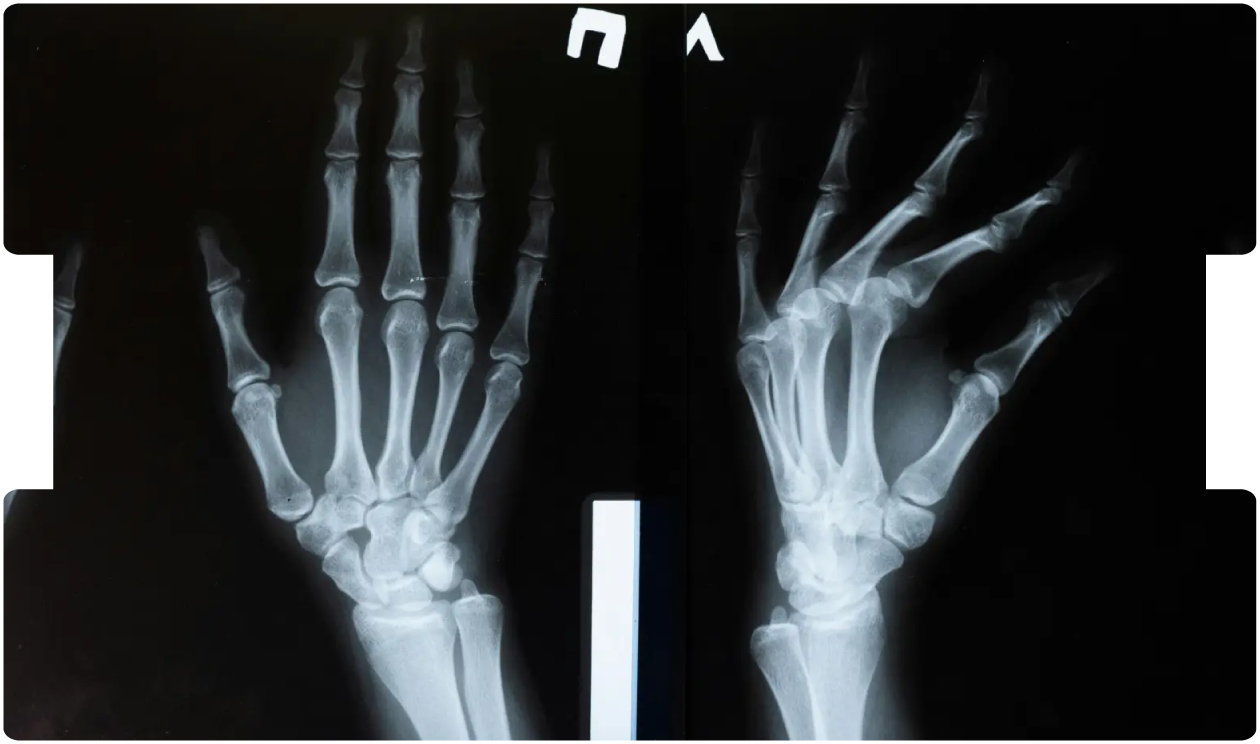

Missed Paediatric Growth Plate Injuries: Medico‑Legal Insights

By Mr Max Mifsud, Consultant Orthopaedic Surgeon

Mr Max Mifsud is a Consultant Orthopaedic Surgeon specialising in complex paediatric trauma at the Nuffield Orthopaedic Centre, Oxford. He frequently provides expert evidence in claims involving growth plate injuries, limb deformities, and mismanaged paediatric fractures.